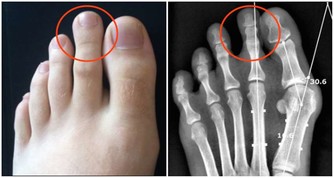

最常見的就是腰部疼痛,這種疼包括絞痛或者鈍痛,不要總認為腎結石的疼痛總是很劇烈,當結石還沒有下落到輸尿管的時候,所導致的疼痛往往不會非常劇烈。

除此之外,結石可能會損壞腎的微小血管,造成血尿,某些人還會表現為尿頻、尿急和尿痛等。